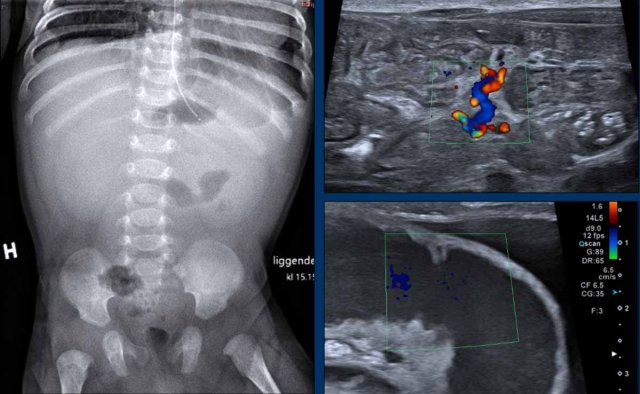

Images

Radiograph of a 2 month old baby with bilious vomiting after diaphragmatic hernia operation. There is very little bowel air consistent with the vomiting and collapsed bowel. On ultrasound ascites and a distended bowel loop with decreased perfusion are seen. In the mesentery a twist of the vessels is seen consistent with volvulus.